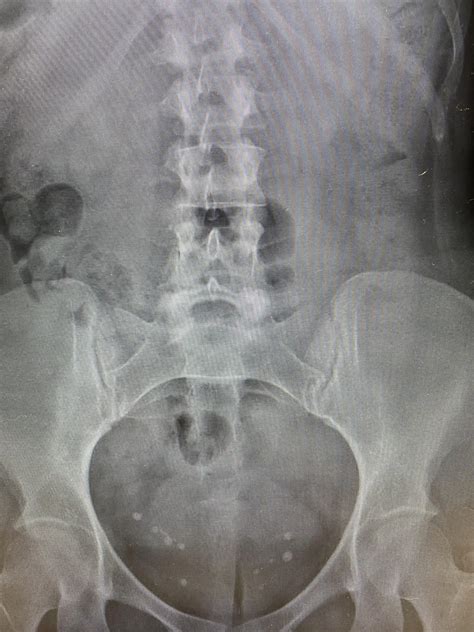

Phleboliths are small, calcified deposits that form within veins. They are typically composed of calcium and other minerals and can vary in size from a few millimeters to several centimeters. These deposits are often incidental findings during imaging studies, such as X-rays, CT scans, or MRIs. While phleboliths can occur in various parts of the body, their presence in the pelvis is particularly noteworthy due to the anatomical complexity of the region.

Detecting phleboliths in the pelvis typically involves imaging techniques that can visualize the calcified deposits. The most common diagnostic methods include:

• X-Rays: Plain radiographs can sometimes detect phleboliths, especially if they are large enough. However, X-rays are less sensitive compared to other imaging modalities.

The clinical significance of phleboliths in the pelvis can vary depending on their size, location, and the underlying cause. In many cases, phleboliths are incidental findings and do not require any specific treatment. However, there are situations where they may indicate an underlying medical condition that warrants further investigation. Some key points to consider include:

• Incidental Findings: Many phleboliths are discovered incidentally during imaging studies performed for other reasons. In such cases, they are often benign and do not require any intervention.